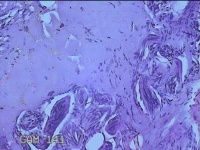

双下肢肿物

性别

男

年龄

41岁

临床诊断

皮脂腺痣

一般病史

双下肢红斑痒一年余。

标本名称

大体所见

灰白暗红色肿物0.8x07x0.3cm一个,表面糜烂。